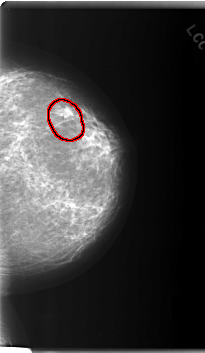

C_0165_1.LEFT_CC

LEFT_CC LINES 5992 PIXELS_PER_LINE 3472 BITS_PER_PIXEL 12 RESOLUTION 50 OVERLAY

FILE: C_0165_1.LEFT_CC.OVERLAY

TOTAL_ABNORMALITIES 1

ABNORMALITY 1

LESION_TYPE MASS SHAPE ROUND MARGINS SPICULATED

ASSESSMENT 5

SUBTLETY 5

PATHOLOGY MALIGNANT

TOTAL_OUTLINES 1

BOUNDARY